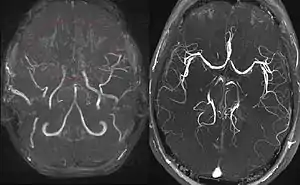

Left: MIP reconstructed MR angiography of a 11-year-old girl with moyamoya disease.

Right: healthy patient, for comparison.

Cerebral angiography is the gold standard of diagnosing moyamoya disease and its progression. According to Suzuki's system, it can be classified into six stages:[15]

Magnetic resonance angiography (MRA) is also useful in diagnosing the disease with good correlation with Suzuki's grading system.[15]